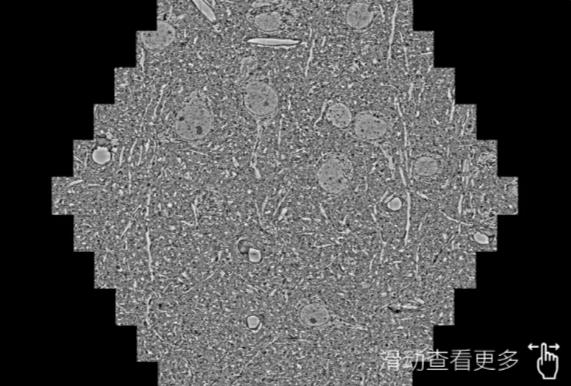

鼠脑切片。左图使用吉安蔡司吉安扫描电镜MultiSEM706对165μmx143pm面积区域成像,耗时仅需1.5秒。右图为鼠脑切片中30μm区域放大效果。样品由芝加哥大学B.Kasthuri提供。

使用蔡司高速吉安扫描电镜MultiSEM对1mm²人脑皮层组织进行高分辨成像,并对其中的各种细胞结构进行三维重构分析。左图展示了2x3mm²组织平面中锥体神经元的三维重构效果。右图显示了局部体积神经元三维重构。图像由哈佛大学chtman实验室提供,渲染图由D. Berger 制作。